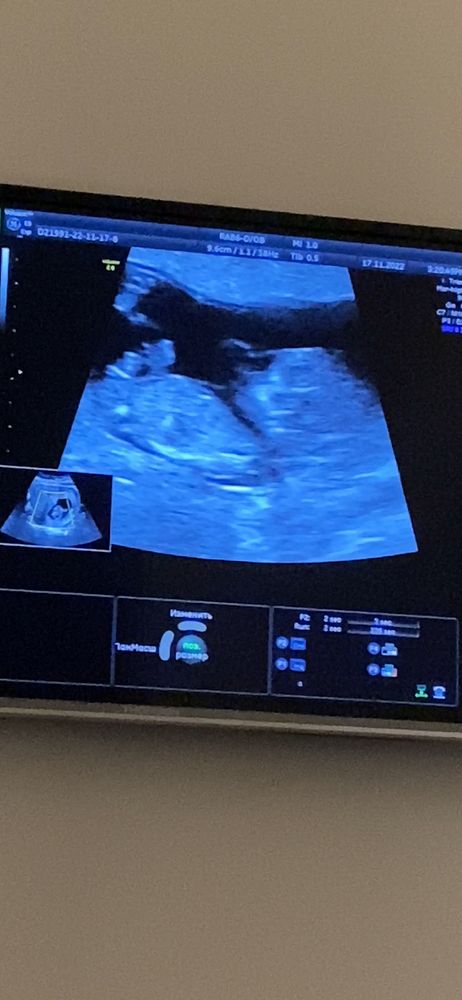

Здесь видно половой бугорок?

бугорок параллельно, думаю, девочка)

Да, кажется, девочка😊 бугорок параллелен позвоночнику.Если я с пуповиной не спутала))

mamadi, а бугорок это разве не то что сверху такое раздвоенное торчит?)

Мария, Изображение Я думаю, вот он)

mamadi, вот и я про него) и мне кажется как будто наверх больше 😄

Мальчик скорее

Первое что пришло в голову- мальчик

Мне кажется, что мальчик, но 100% не утверждаю.

Мальчик,я думаю